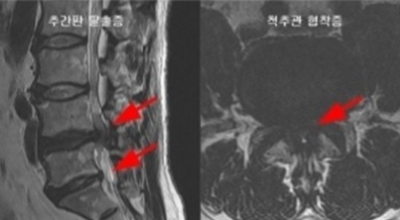

척추관 협착증이란 신경이 지나가는 통로인 척추관이 좁아진 상태를 말하며 척추관 협착증이란 용어는 주로 요추부(허리)에서 사용합니다. 척추관 협착증 환자는 정상에 비해서 척추관이 좁아져 신경이 압박받게 돼요.

정상인 사람은 척추가 완만히 휘어져 있는데 척추관 협착증인 사람은 더 일자로 펴져 있고 정상인 사람의 척추관은 공간이 적당한데 비해 척추관척 협착증인 사람은 척추관이 일그러져 있어요. 척추관 협착증 환자는 자기 공명 영상(MRI)에서 보면 척추관 내 신경을 싸고 있는 경막 안에 정상에서 보이던 뇌척수액이 보이지 않는다는 특징이 있어요.

가장 가장 유명한 구별법은 허리를 앞으로 굽혀보는 것으로 허리디스크일 경우 더 통증이 심해지지만 척추관 협착증일 경우 신경의 압박이 완화되어 통증이 완화되거나 사라지는 것을 경험할 수 있겠습니다. 또 허리디스크 환자는 누워서 두 다리를 들어올릴 수 없지만 척추관 협착증 환자는 누워서 두 다리를 들어올릴 수 있다고 합니다. 이런식으로 누구나 간단히 구별할 수 있겠습니다.